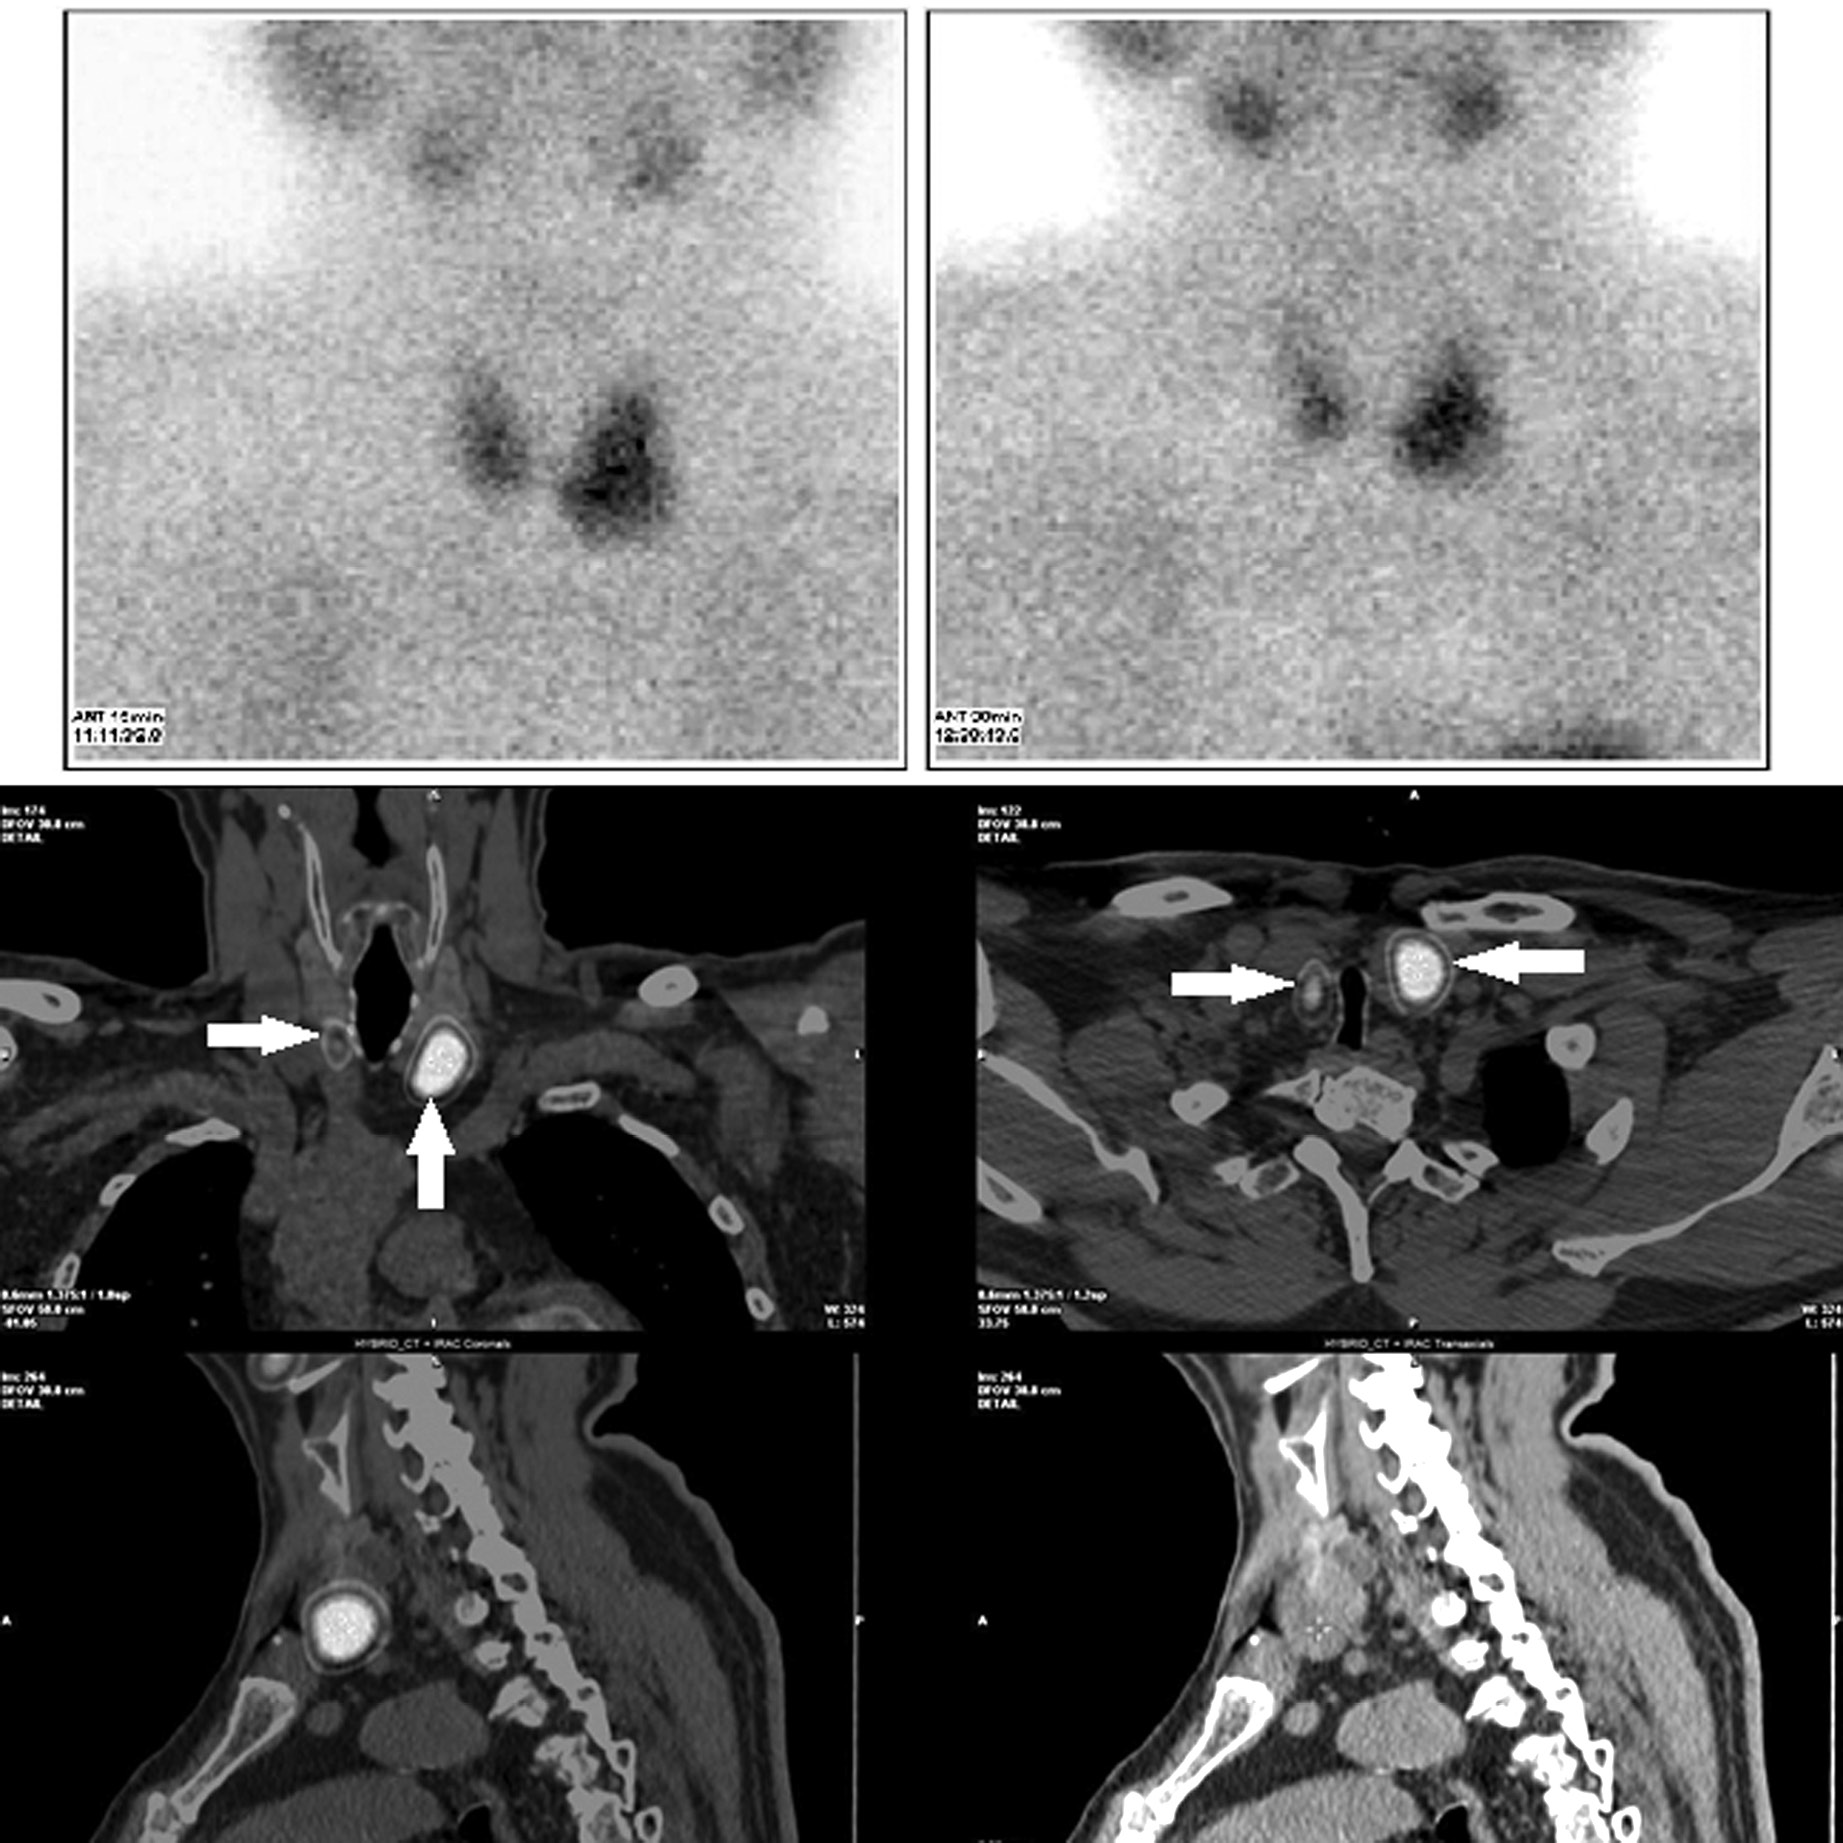

Выполнена сцинтиграфия ОЩЖ с 99mTc-технетрилом (радиоиндиактор активностью 700 МБк), с получением статических изображений области шеи на 15-й и 90-й минутах после введения радиофармпрепарата (РФП). Для уточнения локализации накопления препарата проведена ОФЭКТ/КТ: на ранних и отсроченных снимках определяются участки гиперфиксации радиоиндикатора в проекции нижней трети правой доли и средней и нижней трети левой доли ЩЖ. Позади нижнего полюса правой доли определяется образование с четкими ровными контурами, округлой формы, рентгеновской плотностью 43 HU, линейными размерами 18×14×13 мм, активно накапливающее радиометку, – предположительно аденома ОЩЖ. В нижней трети левой доли (интратиреоидно) определяется образование округлой формы, линейными размерами 29×26×29 мм, с кальцинатами, без четких границ с тканью ЩЖ, рентгеновской плотностью 30 HU, активно накапливающее радиоиндикатор. Также позади средней трети левой доли ЩЖ определяется образование округлой формы, рентгеновской плотностью 32 HU, линейными размерами 16×12×12 мм, не накапливающее радиоиндикатор (узел ЩЖ? лимфатический узел?). В других областях шеи и верхнего средостения патологического очагового накопления радиоиндикатора не выявлено (рис. 1).

Рис. 1. Верхний ряд – планарная сцинтиграфия через 15 и 90 мин после введения РФП; нижний ряд – ОФЭКТ/КТ через 90 мин; Стрелкой (→) отмечены зоны интенсивного накопления РФП в проекции правой нижней ОЩЖ и узла в нижнем полюсе левой доли ЩЖ.

2. Рис. 1. Верхний ряд – планарная сцинтиграфия через 15 и 90 мин после введения РФП; нижний ряд – ОФЭКТ/КТ через 90 мин; Стрелкой (→) отмечены зоны интенсивного накопления РФП в проекции правой нижней ОЩЖ и узла в нижнем полюсе левой доли ЩЖ. | |